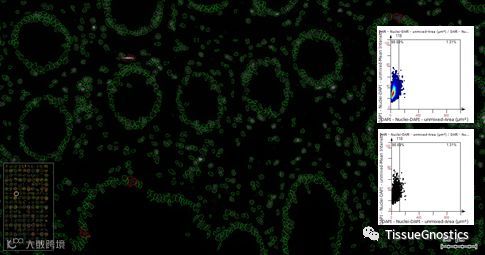

在组织原位,存在核形态不规则、核叠加、核黏连等现象,导致对细胞核内信号及细胞质内信号的定量分析产生误差。TissueFAXSCytometry可以根据细胞核大小与形态等参数,结合散点图的设门圈选,与原始图像的实时联动校验,排除对分析结果可能产生误差的数据。另外,具有热力图展示功能,在二维散点图的基础上,利用不同颜色标注了数据的聚集程度,为设置Cutoff及Gate提供更多的参考标准。

下图红色标记的是面积较大的非统计分析数据部分。

下图为DAPI通道细胞核识别区域,与620通道进行叠加。根据细胞质是否有620通道的Marker染色,以及染色的强弱/染色的形态,综合判断是否为细胞质染色阳性的细胞表型。通过指定细胞核周的判读半径及强度阈值,可以准确识别620通道阳性细胞。

下图中标记黄色,为符合染色强度与面积形态的620通道阳性细胞。二维散点图横坐标为染色面积,纵坐标为染色强度。